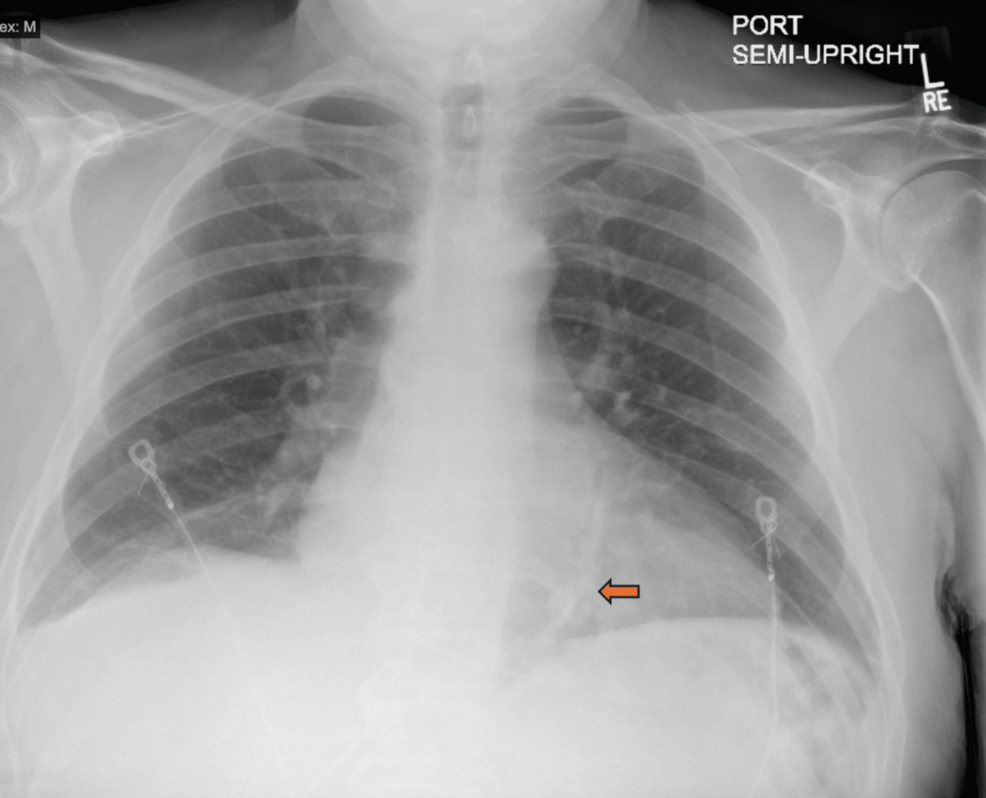

The difficulty in diagnosing this condition is highlighted in a reported case of a 57-year-old female who presented with worsening shortness of breath and volume overload. While her chest CT showed pericardial calcifications and effusion, it was the subsequent right heart catheterization that provided the findings necessary to confirm a diagnosis of constrictive pericarditis (as detailed in Cureus).

Imaging can provide clues; for example, chest computed tomography (CT) may reveal pericardial calcifications or pericardial effusion. However, imaging alone isn’t always enough to confirm the physiological impact on the heart’s function.